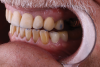

A 75-year-old man presented to the office with severe anterior tooth wear (Figure 2). After meticulous record-taking and thorough planning, a treatment plan was established to rehabilitate the patient to prevent further breakdown. The treatment plan consisted of crowns for teeth Nos. 4 through 13, 20, 21, 28, and 29 coupled with anterior incisal composites for teeth Nos. 22 through 27. Composites were utilized for cost savings to the patient and as a way to establish a more stable occlusion. It was explained to the patient that the composites could be transitioned to veneers at a later date if and when he desired to do so.